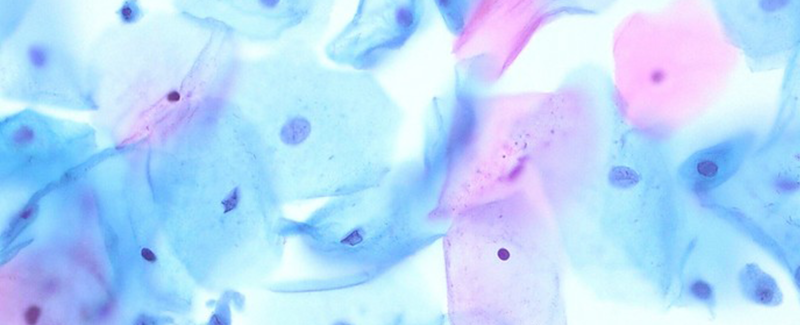

BIOGNOST RAPID PAP STAINING KIT SUPPORTS EARLY DIAGNOSIS OF CERVICAL CANCER

January is Cervical Cancer Awareness month, dedicated to raising awareness of cervical cancer. This [...]